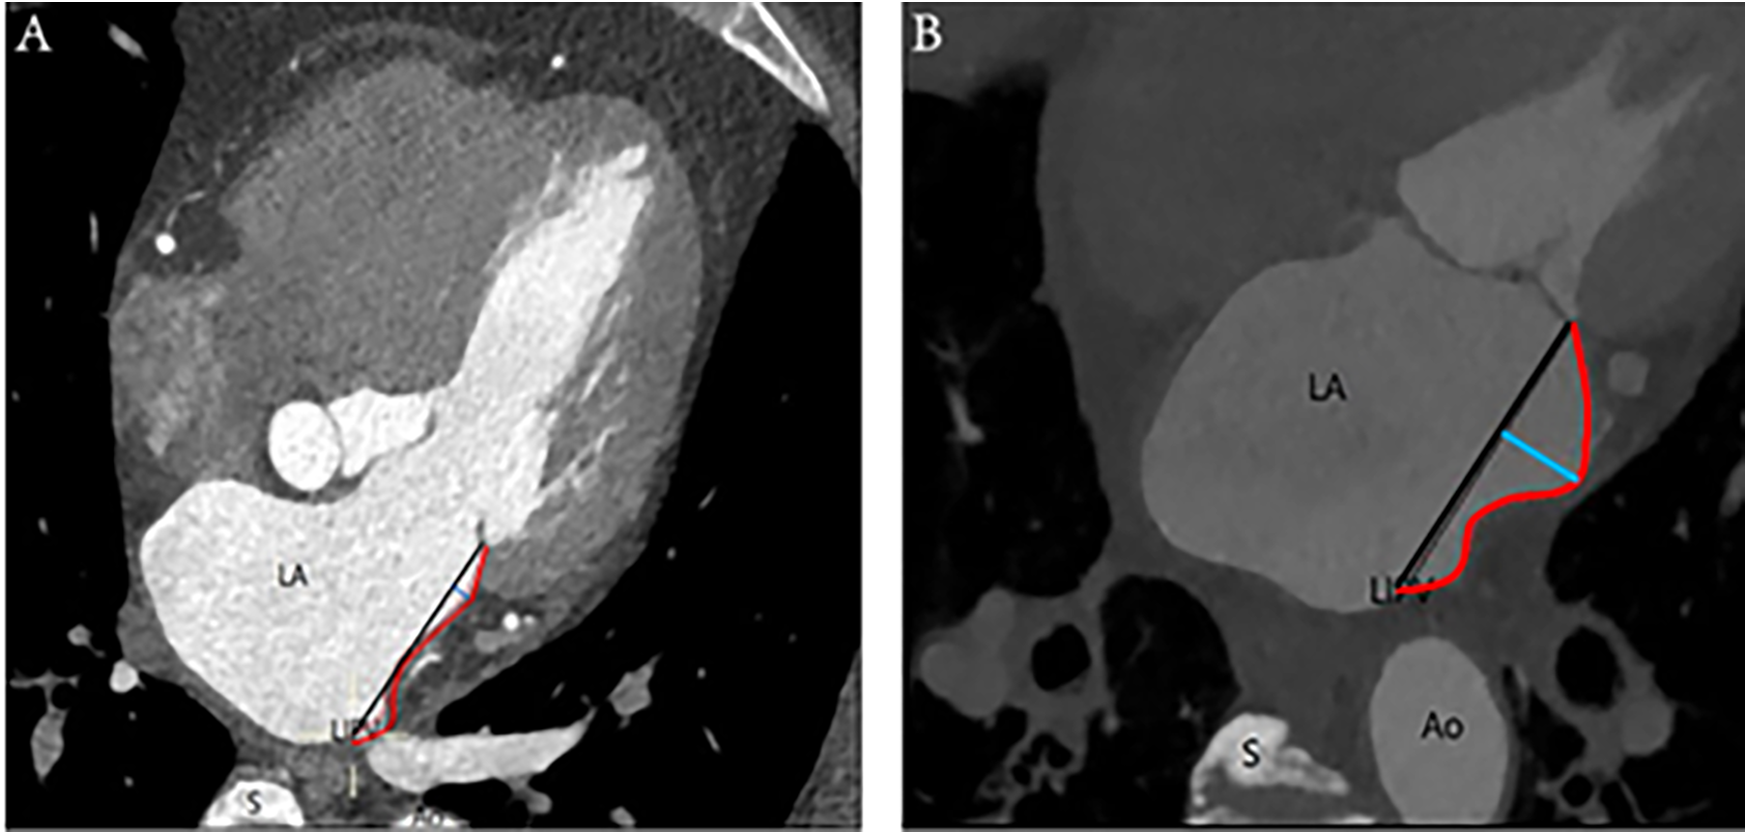

Depths ≤2 mm characterized the MI as linear, whereas depths >2 mm designated the MI as curved, based on clinical observation and anatomical experience (Figure 1).

Figure 1

Linear and curved MI: (A) On the left is an illustration of a linear-shaped MI, whereas (B) on the right is a depiction of a curved-shaped MI. The annotations are as follows: Ao, aorta; LA, left atrium; LIPV, left inferior pulmonary vein; S, spine; red curve, distance of MI; black straight line, length of MI; blue straight line, depth of MI.